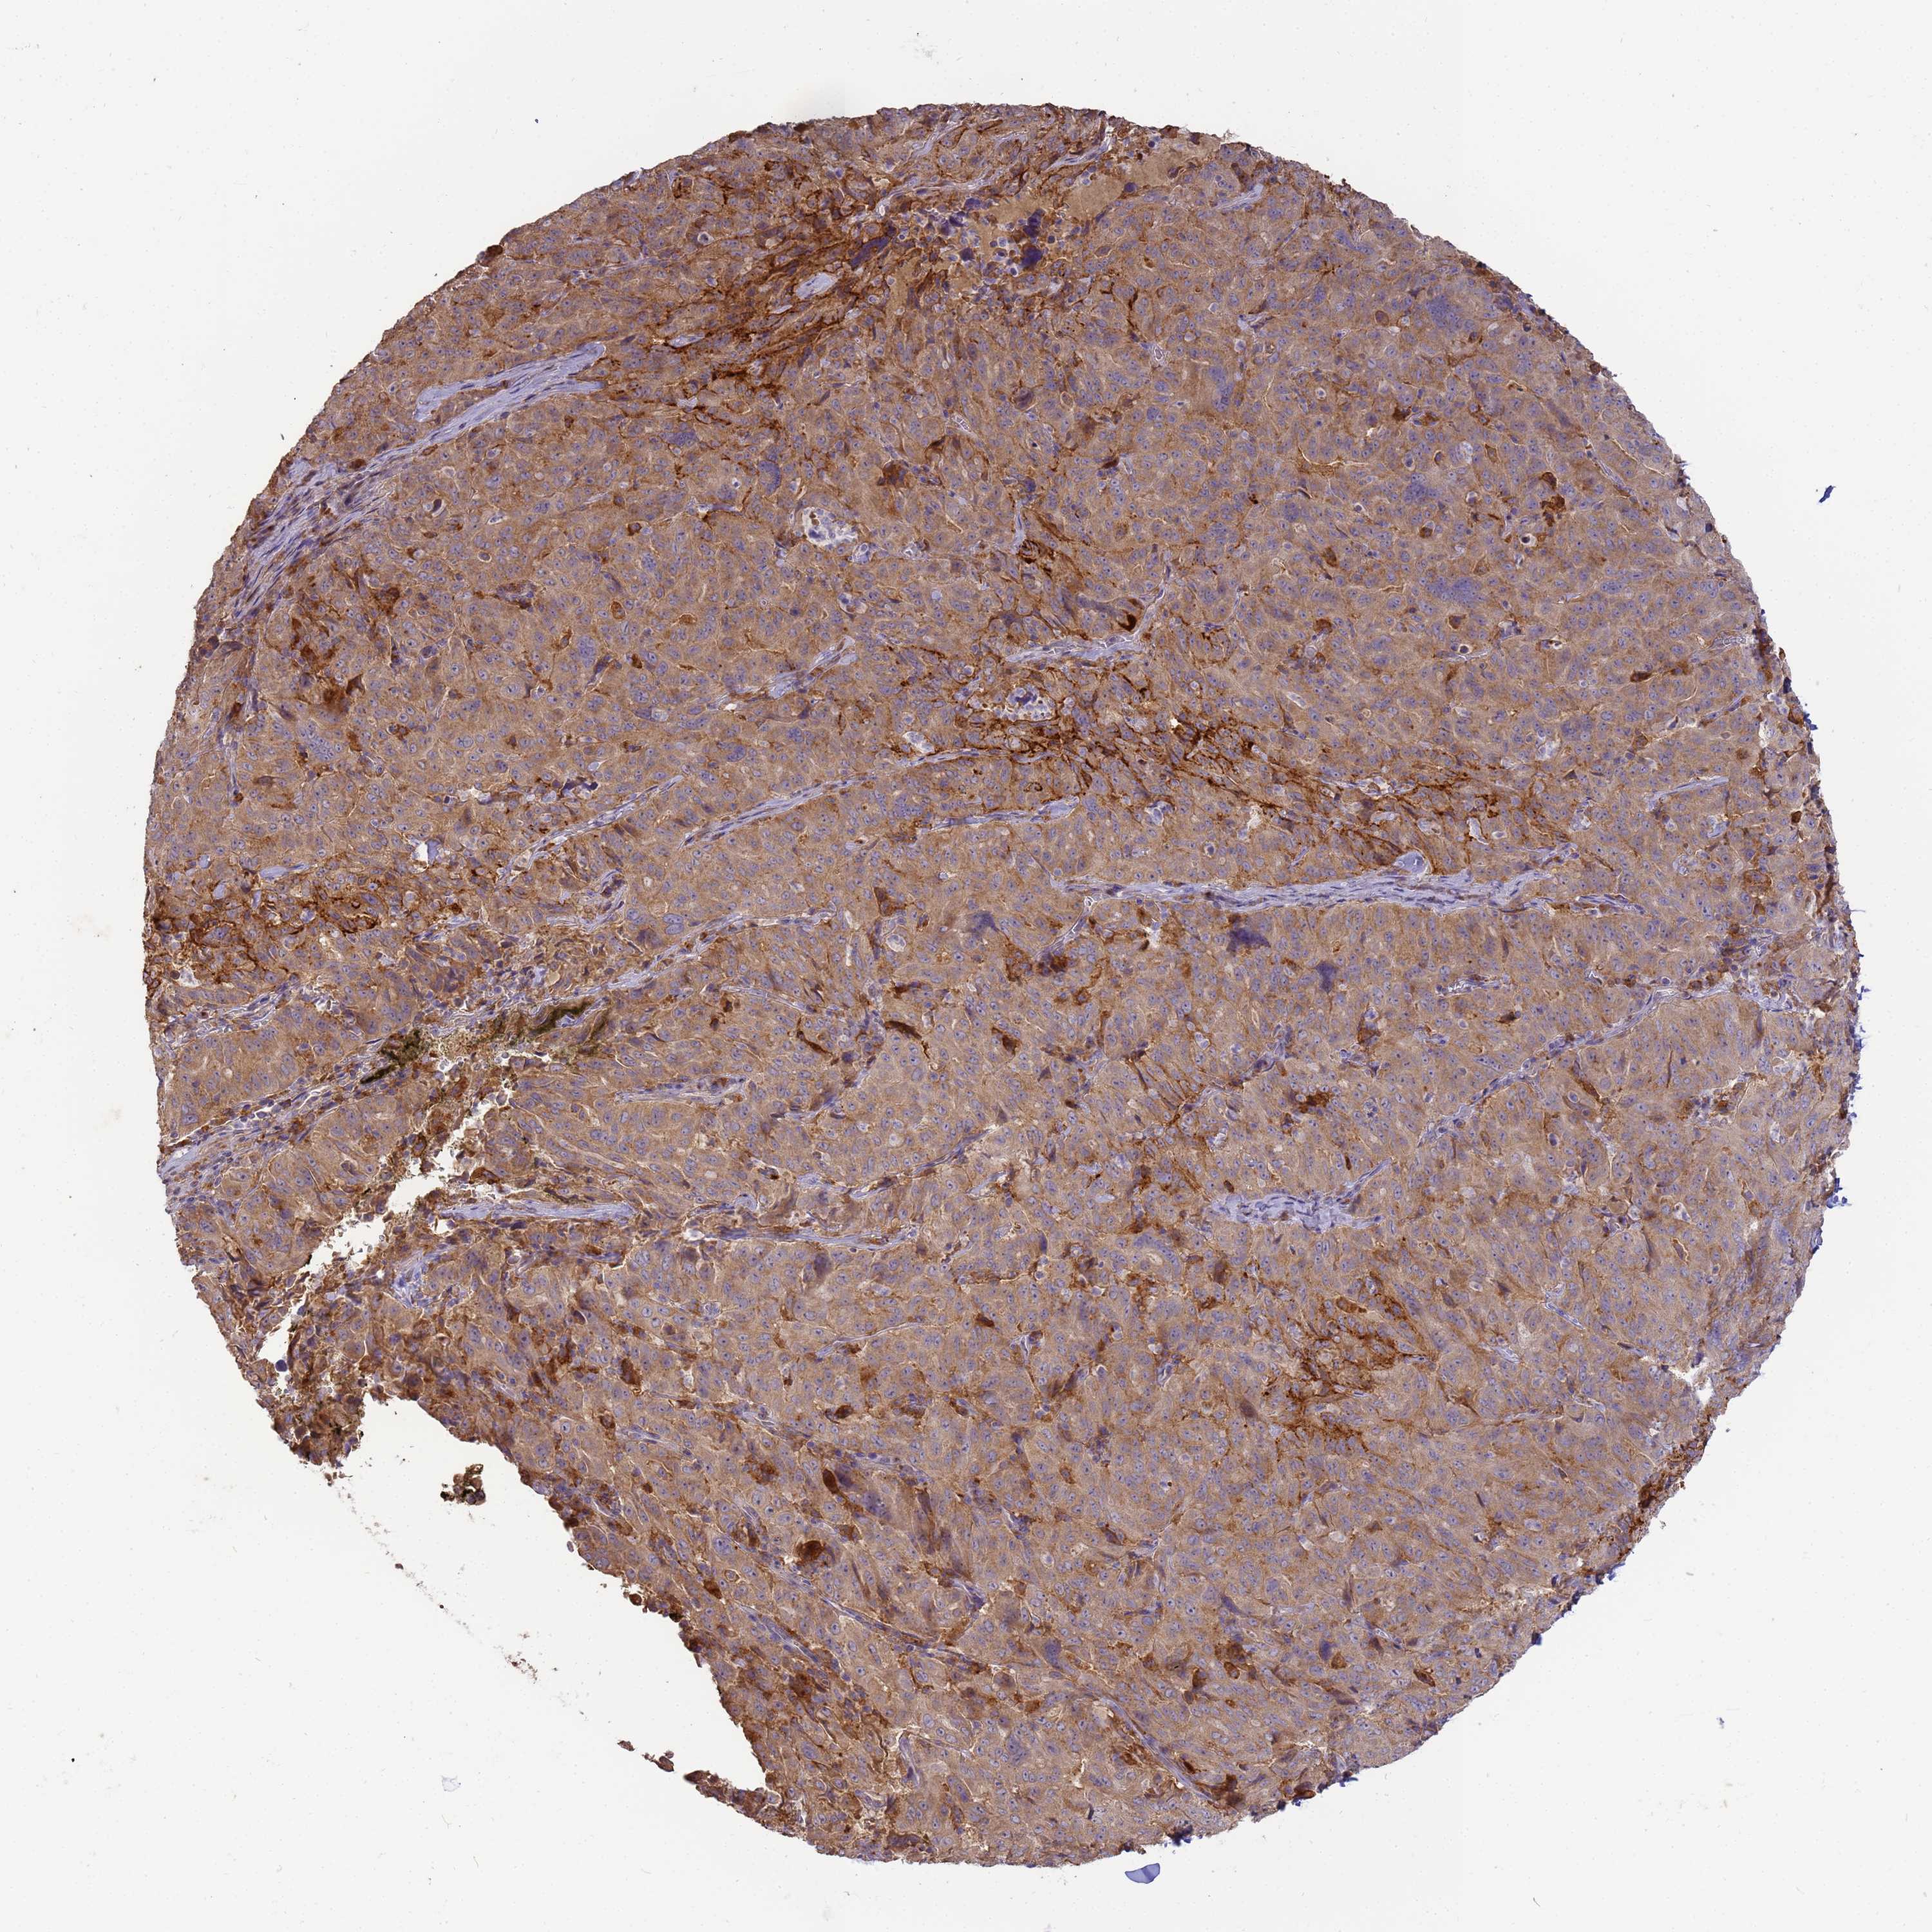

PANCREATIC CANCER - Protein expressioni

A mouse-over function shows sample information and annotation data. Click on an image to view it in a full screen mode. Samples can be filtered based on level of antibody staining by selecting one or several of the following categories: high, medium, low and not detected. The assay and annotation is described here.

Note that samples used for immunohistochemistry by the Human Protein Atlas do not correspond to samples in the TCGA dataset.

Antibody stainingi

Antibody staining in the annotated cell types in the current human tissue is reported as not detected, low, medium, or high, based on conventional immunohistochemistry profiling in selected tissues. This score is based on the combination of the staining intensity and fraction of stained cells.

Each image is clickable and will lead to virtual microscopy that enables deeper exploration of all samples and also displays staining intensity scores, fraction scores and subcellular localization as well as patient and tissue information for each sample.

Antibody HPA040445

Antibody CAB034464

Staining

High

Medium

Low

Not detected

Intensity

Strong

Moderate

Weak

Negative

Quantity

>75%

75%-25%

<25%

None

Location

Nuclear

Cytoplasmic/membranous

Cytoplasmic/membranous,nuclear

Adenocarcinoma, NOS